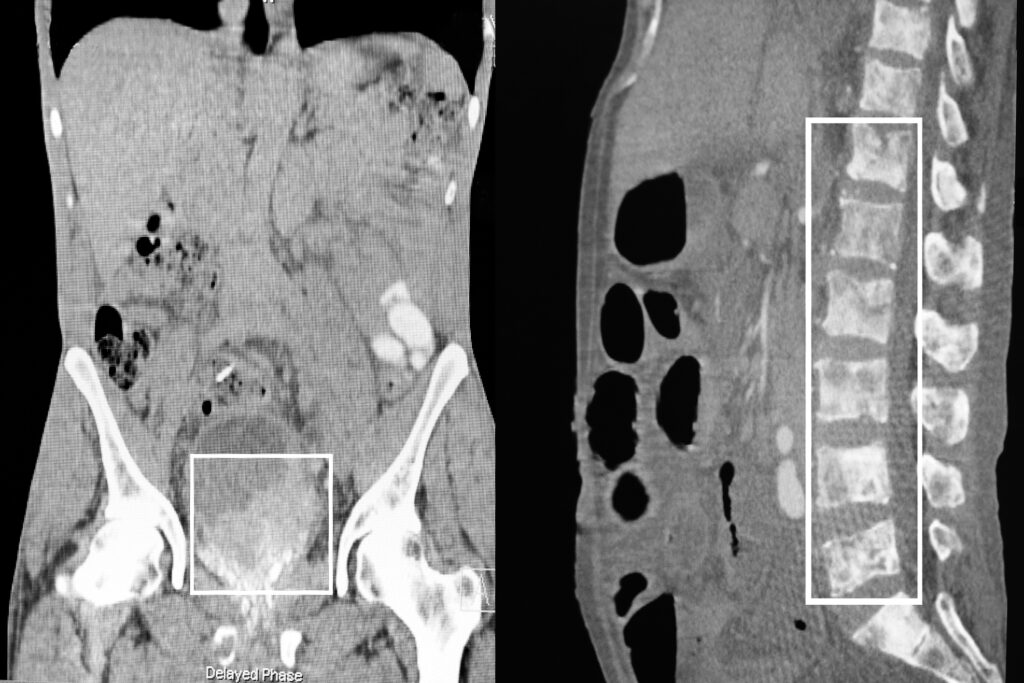

Response assessment is integral to the adaptive design. During active treatment, each cycle is followed by quantitative post-therapy SPECT/CT (24–72 hours) to assess the relative change in PSMA-avid tumour burden and to perform single-time-point dosimetry. During treatment holidays, surveillance shifts to PSMA PET/CT every 12 weeks alongside PSA, using RECIP criteria. Patients achieving near-complete biochemical and imaging responses can pause therapy; if progression is detected, treatment resumes using the original cycle-1 SPECT/CT as the radiographic baseline for subsequent comparisons.